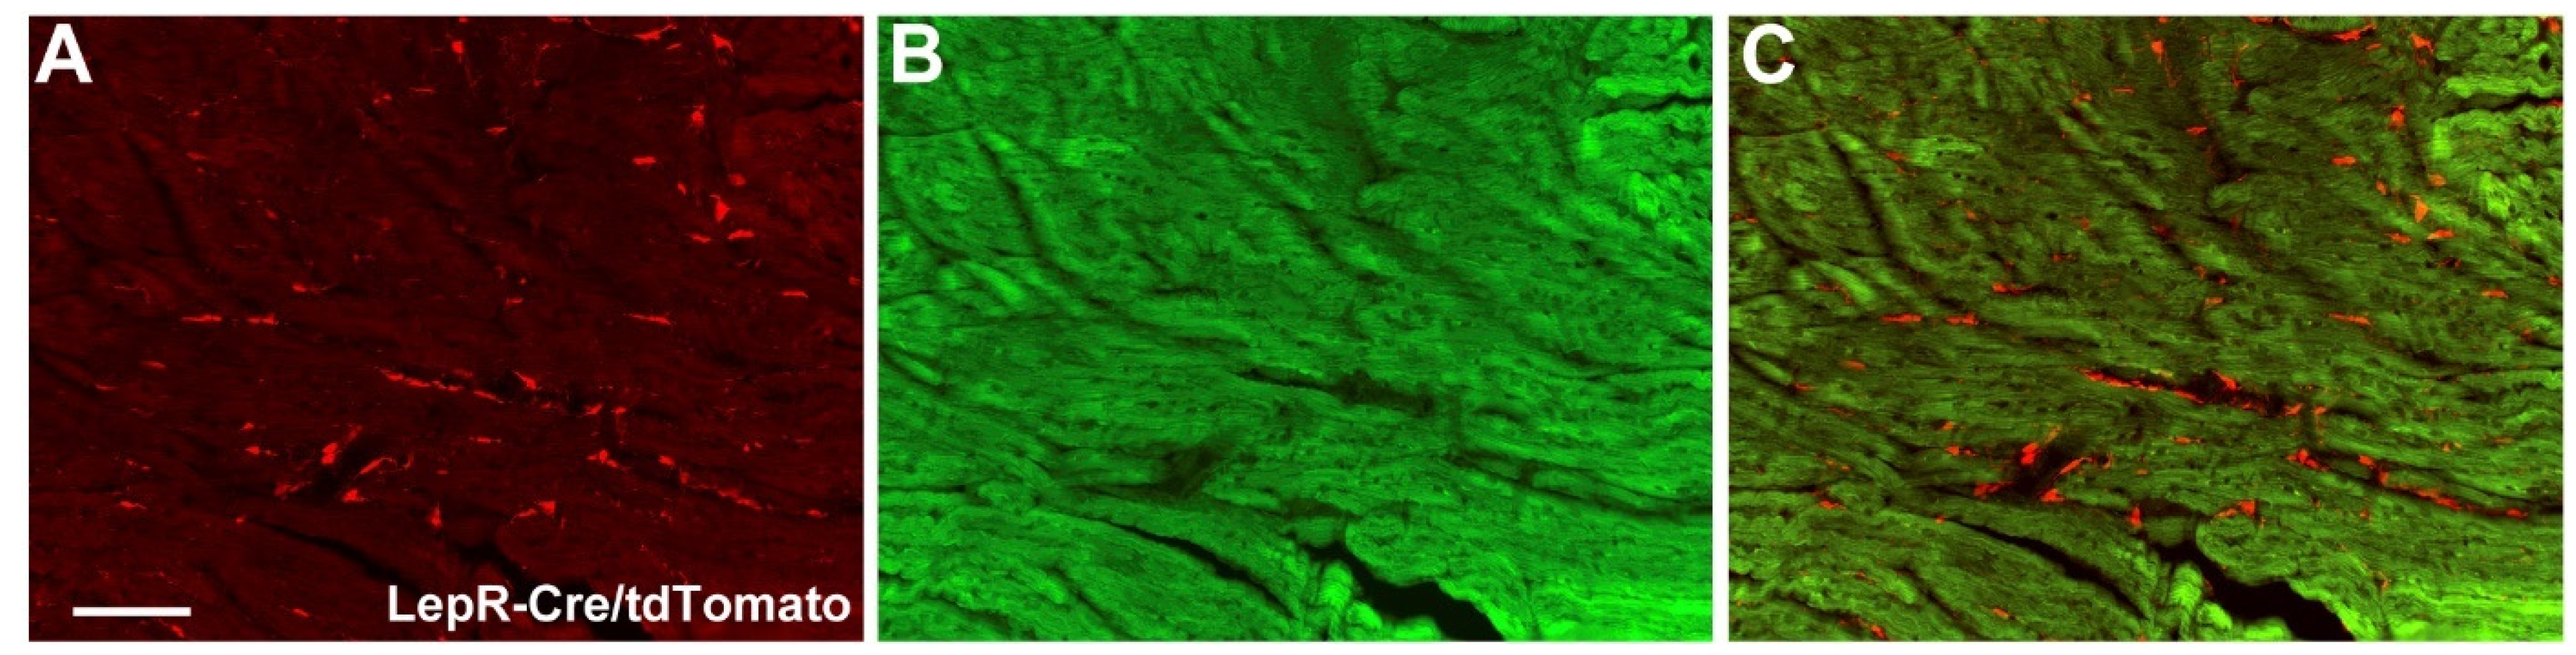

2.3. Cardiac Abnormalities and Decreased Survival Rate in Aging LepR∆SOCS3 Mice

4.1. Animals